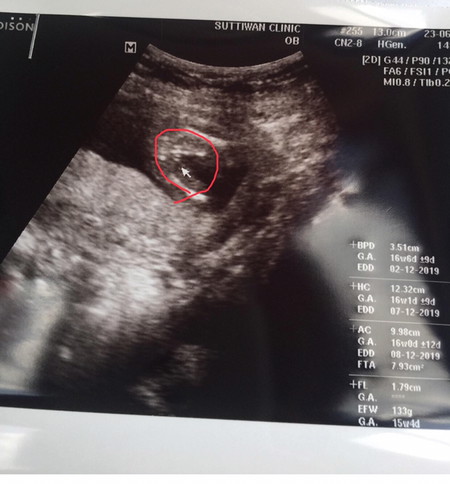

คุณแม่ค่ะ เราพึ่งพบคุณหมอมาค่ะ. แบบนี้ที่วงกลมไว้ เพศอะไรค่ะ. คุณแม่ช่วยดูให้ทีค่ะ. ขอบคุณค่ะ

ผู้หญิง100%จ้า เป็นกลีบๆ รูปคล้ายๆของลูกเราเลยคะ